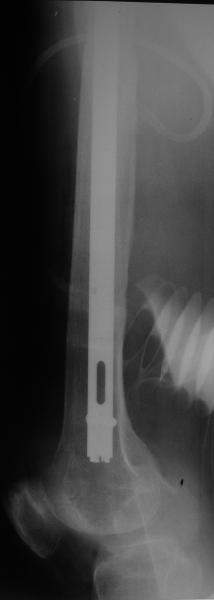

Спасибо за обсуждение. После нескольких дней тракции аппаратом сделали. Попытка закрытой репозиции не удалась из-за смещения по ширине, мешали фрагменты цемента. После их удаления репозиция получилась. Еще убрали немного цемента с ножки по латерльной стороне, чтобы обнажить 40-50 мм ее дистальной части, для плотной посадки гвоздя. Дальнейшее введение гвоздя было несложным. Протез показался нам стабильным в проксимальной части как латерально, так и медиально. Картинки в приложении.

THX for the discussion. After few days of traction by ex-fix the surgery was performed. An attempt of closed nailing was unsuccesful because of fragment translation, which was blocked by cement fragments. After removal of broken cement pieces reduction was reached "automagically". Also some cement from lateral part was removed by

chisel to expose distal 40-50 mm of the stem to allow tight fit of the nail. Further fixation by the nail was pretty easy and straightforward. Images attached. The stem looked stable in its proximal part both laterally and medially. Comments/critics are welcome.

I would like to ask one little question, you said 'tight fit of the nail' to the femoral stem, since all the rotational stability of the system (distal fragment with nail and locking screws) comes from that point, is it reliable?.

* distal fixation of the nail is based near only on two screws : are they sufficient to secure a good stability before fracture consolidation?